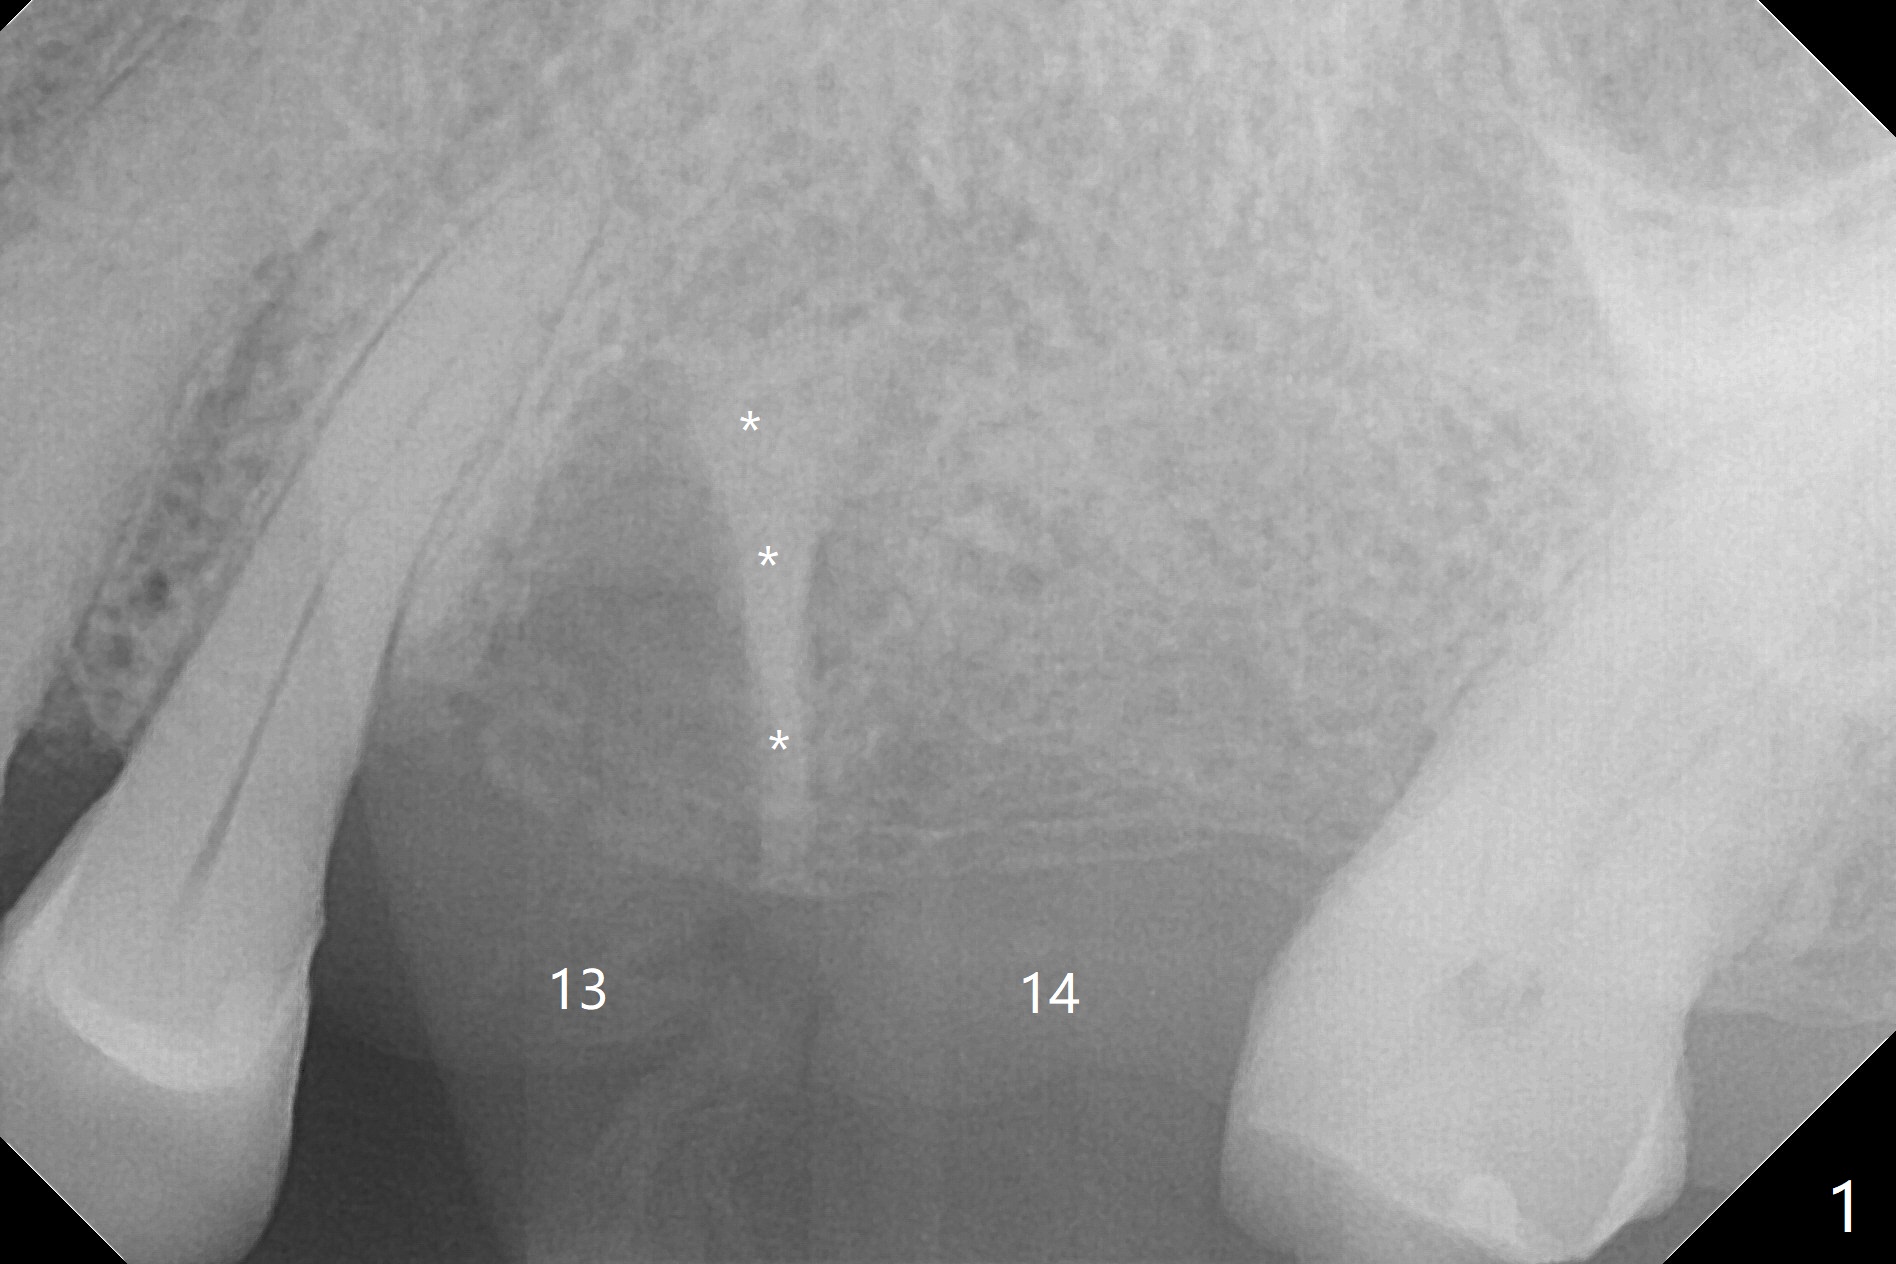

After extraction of the tooth #13 residual root, the bone in the distal wall of the socket looks white. Intraop PA rules out root structure (Fig.1 *). Osteotomy is conducted according to drill sequence. Bitewings are taken to check implant placement level (Fig.2,3). Following implant level adjustment and healing abutment installment (Fig.4,5 (*: bone graft)), the implant at #13 is found to be close the root of #12 (Fig.6 *), i.e., not parallel to the implant at #14. Introspectively, 2.2x10 mm drill seems to be long. When it touches the bone, the cylinder portion of the drill (Fig.7 red) does not engage into the sleeve (green). When it goes into the bone, it may have been deflected mesial due to the slope of the distal wall of the socket (hard bone, Fig.8 open arrow)). If a shorter drill (such as 2.2x7.3 or 8.5 mm) were used (Fig.9), the deflection would be minimal if drilling is slow (Fig.10). CT taken 1 week postop shows that the implant at #13 is approximately 1 mm near the root of the tooth #12, but the neurovascular bundle to the latter seems not to have been interrupted (Fig.11,12). The buccopalatal trajectory at #14 is within normal limit (Fig.11,13 (B: buccal)). There is no periapical radiolucency at #12 five months postop (Fig.14). However the cemented abutments are incompletely seated (<). The patient is reluctant to return for impression 17 months postop (due to coronavirus); with attention, the same abutment at #13 is reseated completely; an abutment with longer cuff and narrower diameter is also seated completely (Fig.15).